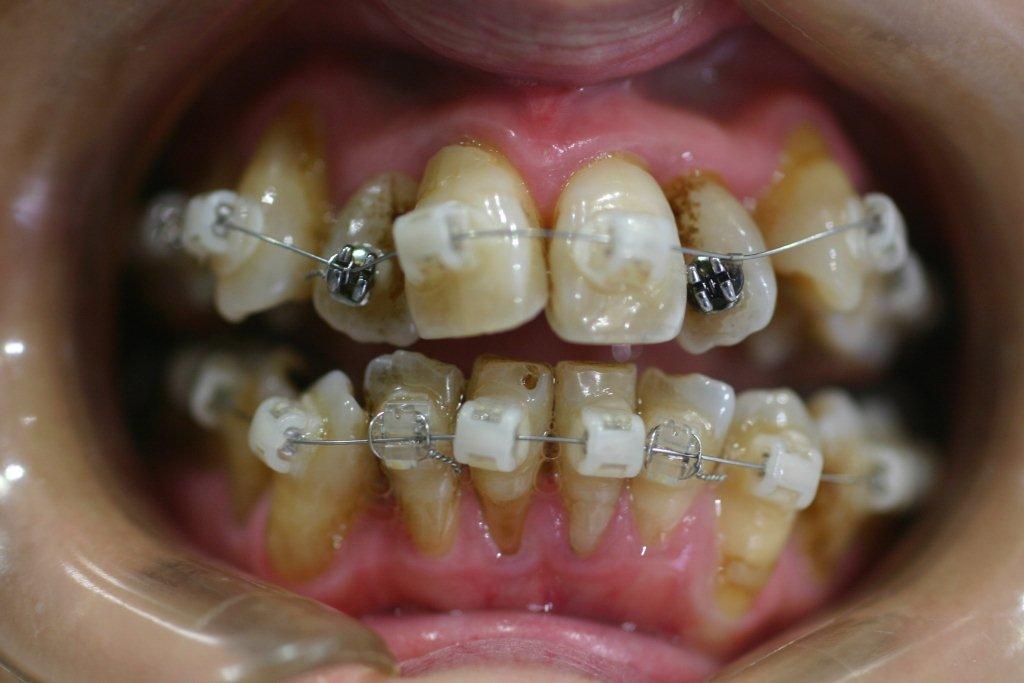

50代で歯周病のもある患者様の矯正症例

Before

After

特に奥歯が抜いてあるため、奥歯の本数がこれ以上少なく出来ない方です。これだけの強い不正咬合を非抜歯で治した症例です。年齢的にも難しい症例でしたが、かなりきれいに治り、 患者様自信が大変満足された症例です。

年齢 50代

治療期間 1年6ヶ月

治療費用 1,000,000円

治療のリスク 歯周病が進行するリスクがある